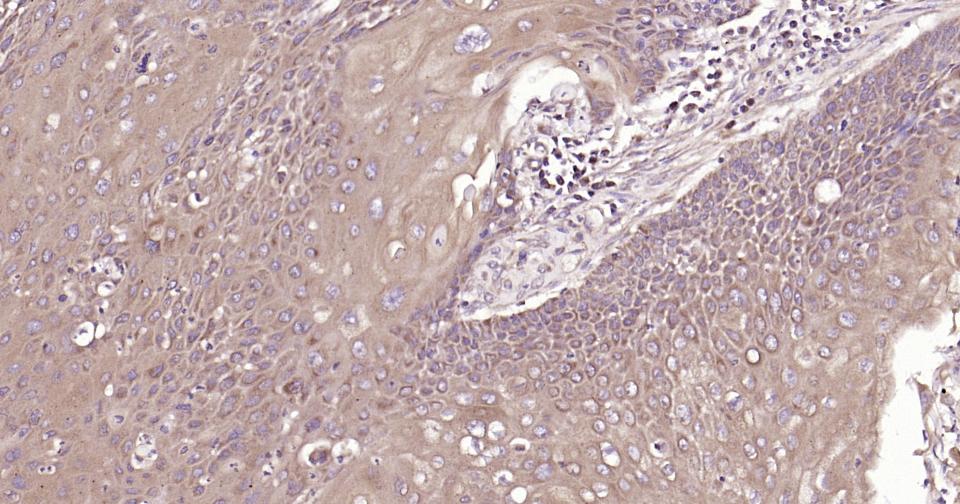

| IHC-P | Human, Mouse, Rat | Rabbit | 1:400-800 |